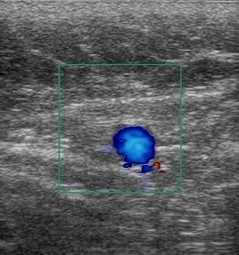

Повышения вязкости крови ведет к появлению эхогенности внутрисосудистого содержимого. Стенка у вен намного тоньше артериальной, и в норме всегда меньше 1 мм, не имеет деления на слои. Артериальная хорошо видна, дифференциация на слои отчетливая. При обследовании вен оценивают ее стенку, диаметр просвета, однородность просвета, внутрипросветные структуры, реакцию на функциональные пробы, как в черно-белом режиме, так и с цветовым кодированием кровотока. При проведении проб, на вдохе вены расширяются, работоспособные клапаны не пропускают кровь в противоположном направлении (от сердца к периферии), что отражается при цветовом кодировании кровотока как отсутствие цвета, в патологии же, цвет меняется на противоположный.

колышашихся парусов прерывают венозный просвет. Очень наглядно видна работа клапанов при

функциональных пробах и цветовом кодировании кровотока, когда в норме цвет исчезает, а при

несостоятельности клапана он меняется на противоположный.